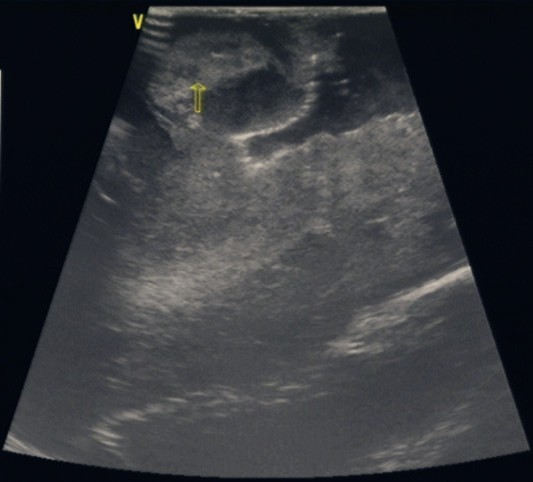

當(dāng)天,在B超室的大力支持和配合下,手術(shù)順利地進(jìn)行。術(shù)中應(yīng)用我院平常的床邊B超機(jī),選擇一個(gè)與術(shù)區(qū)相當(dāng)?shù)?span>B超探頭,裹上無(wú)菌膜即可使用。在切除腫瘤過程中,用B超探頭貼近術(shù)區(qū)探測(cè)腫瘤的范圍及位置,在B超引導(dǎo)下一步步切除腫瘤。當(dāng)手術(shù)行將結(jié)束時(shí),再次應(yīng)用B超探測(cè),清楚地發(fā)現(xiàn)腫瘤殘留,并進(jìn)一步切除干凈。結(jié)果,本例手術(shù)切除了95%以上的腫瘤組織,取得了圓滿的成功。

1. 腦腫瘤術(shù)中B超應(yīng)用

2.術(shù)中B超探測(cè)腫瘤